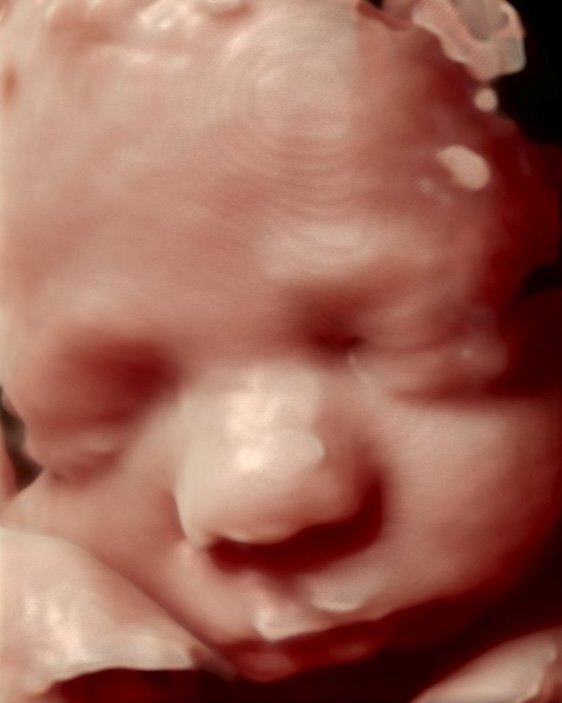

La ecografía 3D, 4D y 5D nos ofrece una visión cada vez más detallada y realista de nuestro bebé durante el embarazo. Con la 3D podemos apreciar su rostro y cuerpo en tres dimensiones, mientras que la 4D nos permite verlo moverse en tiempo real. La 5D lleva esta experiencia al siguiente nivel, proporcionando imágenes aún más nítidas y realistas, casi como si pudiéramos tocar al bebé. Estas tecnologías no solo nos permiten conectarnos emocionalmente con nuestro hijo, sino que también nos brindan tranquilidad al confirmar su buen desarrollo.

El ultrasonido 3D nos permite ver al bebé como nunca antes lo habíamos imaginado. Es como tener una pequeña ventana a su mundo, donde podrás apreciar sus características únicas y sentir una conexión aún más profunda. Mientras que en las ecografías tradicionales vemos una imagen plana, con el 3D podemos disfrutar de una vista tridimensional de su rostro, sus manos, sus pies.

Con el ultrasonido 5D, podemos tener una imagen aún más detallada y realista del pequeño. Es como si pudiéramos tocarlo con la mirada. Esta tecnología nos brinda una tranquilidad inmensa al saber que nuestro bebé se está desarrollando de manera saludable.